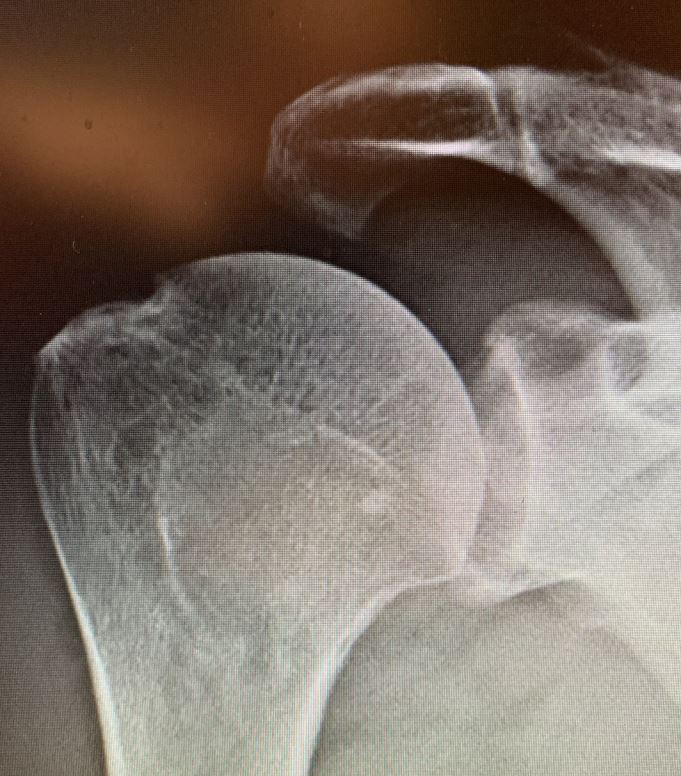

Das Schultergelenk verweigert den Dienst

Röntgenaufnahme Schultergelenk/© A. Schuh, Die Leitlinien für Ärztinnen und Ärzte, Facharzttraining Allgemeinmedizin, Eine Hand die schreibt mit Computer daneben/© Chainarong Prasertthai / Getty Images / iStock (Symbolbild mit Fotomodell), Ältere Frau mit schmerzender Hand/© Evrymmnt / stock.adobe.com (Symbolbild mit Fotomodell), Mädchen bekommt eine Spritze in den Oberarm/© Photographee.eu / stock.adobe.com (Symbolbild mit Fotomodell), Ältere Frau mit Hanteln/© Satjawat / Stock.adobe.com (Symbolbild mit Fotomodell), EKG befunden mit System - EKG Essential/© Springer Medizin Verlag GmbH